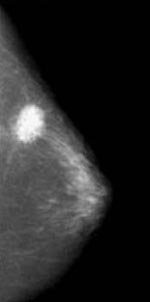

- Mamografías

Es

la representación radiológica del tejido blando de la glándula

mamaria.

Se inició en el año 1913 y siempre se realizan dos proyecciones; una cráneo-caudal y otra oblicua.

Tiene una sensibilidad del 90% y hoy en día se empieza a utilizar la mamografía digital con lo que se mejorará la imagen y por lo tanto el diagnóstico.

Dentro de las indicaciones se encuentra el despistaje del cáncer de mama, y la evaluación de los tumores palpables.

Entre las limitaciones están los falsos negativos (10-15%), y los errores de interpretación. En ocasiones no aparece el tumor en la mamografía debido a su localización, a una mala técnica (poca compresión...) y a que hay tumores que no tienen representación radiográfica (son los Cáncer mudos).

Como ventajas tiene el descubrimiento de los Tumores no palpables, el descubrimiento de las pacientes de riesgo, y que es la técnica de elección en las campañas de diagnostico precoz del cáncer de mama.

Entre las desventajas figura la baja rentabilidad en mujeres jóvenes, el coste de la exploración, y la radiación recibida por parte de la mujer.

Mucho se ha hablado sobre el riesgo que produce la radiación al realizarse la mamografía. La dosis recibida por mamografía es de 0.1-0.3 rads. Se calcula que una mama sometida a 90 rads tiene 2-4 veces más posibilidades de desarrollar un Cáncer de mama.

Una mama sometida a mamografía anual durante 30 años no recibe una dosis considerada de riesgo. Se considera que tiene el mismo riesgo que viajar por carretera durante 350 Km o 4000 en avión. Como se ha dicho en repetidas ocasiones “el mayor riesgo de una mamografía es el no hacérsela”.